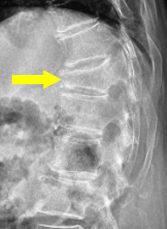

びまん性特発性骨増殖症

せぼね(脊椎)は7個の頚椎、12個の胸椎、5個の腰椎と仙椎から構成されます。腰椎は主に5つの骨と、間にあるクッションのような椎間板、また神経組織が通っている脊柱管から成り立っています。びまん性特発性骨増殖症とは、前縦靭帯を中心に骨化が広範に起こることで、本来個々に動くべき脊椎が4つ以上くっついてしまう病気です。肥満や糖尿病などの生活習慣病との関連が指摘されており、近年増加傾向にあります。

体幹の柔軟性が失われたり、転倒により骨折を生じやすいことがあります。非常に不安定性が強い骨折となったり、軽微な転倒後の数ヶ月後に神経障害を生じたりすることがあるので注意が必要です。

脊椎や靭帯などの骨化の程度や、骨折の有無を判断するためにX線検査やCT検査、MRI検査を行う場合があります。骨折の有無は、X線検査のみでは診断が難しいことも少なくありません。また、生活習慣病との関連が指摘されているため、手足の血流や動脈硬化の有無を評価するため両手足の血圧を測ったり、骨脆弱性を評価するために骨密度検査を行うことがあります。